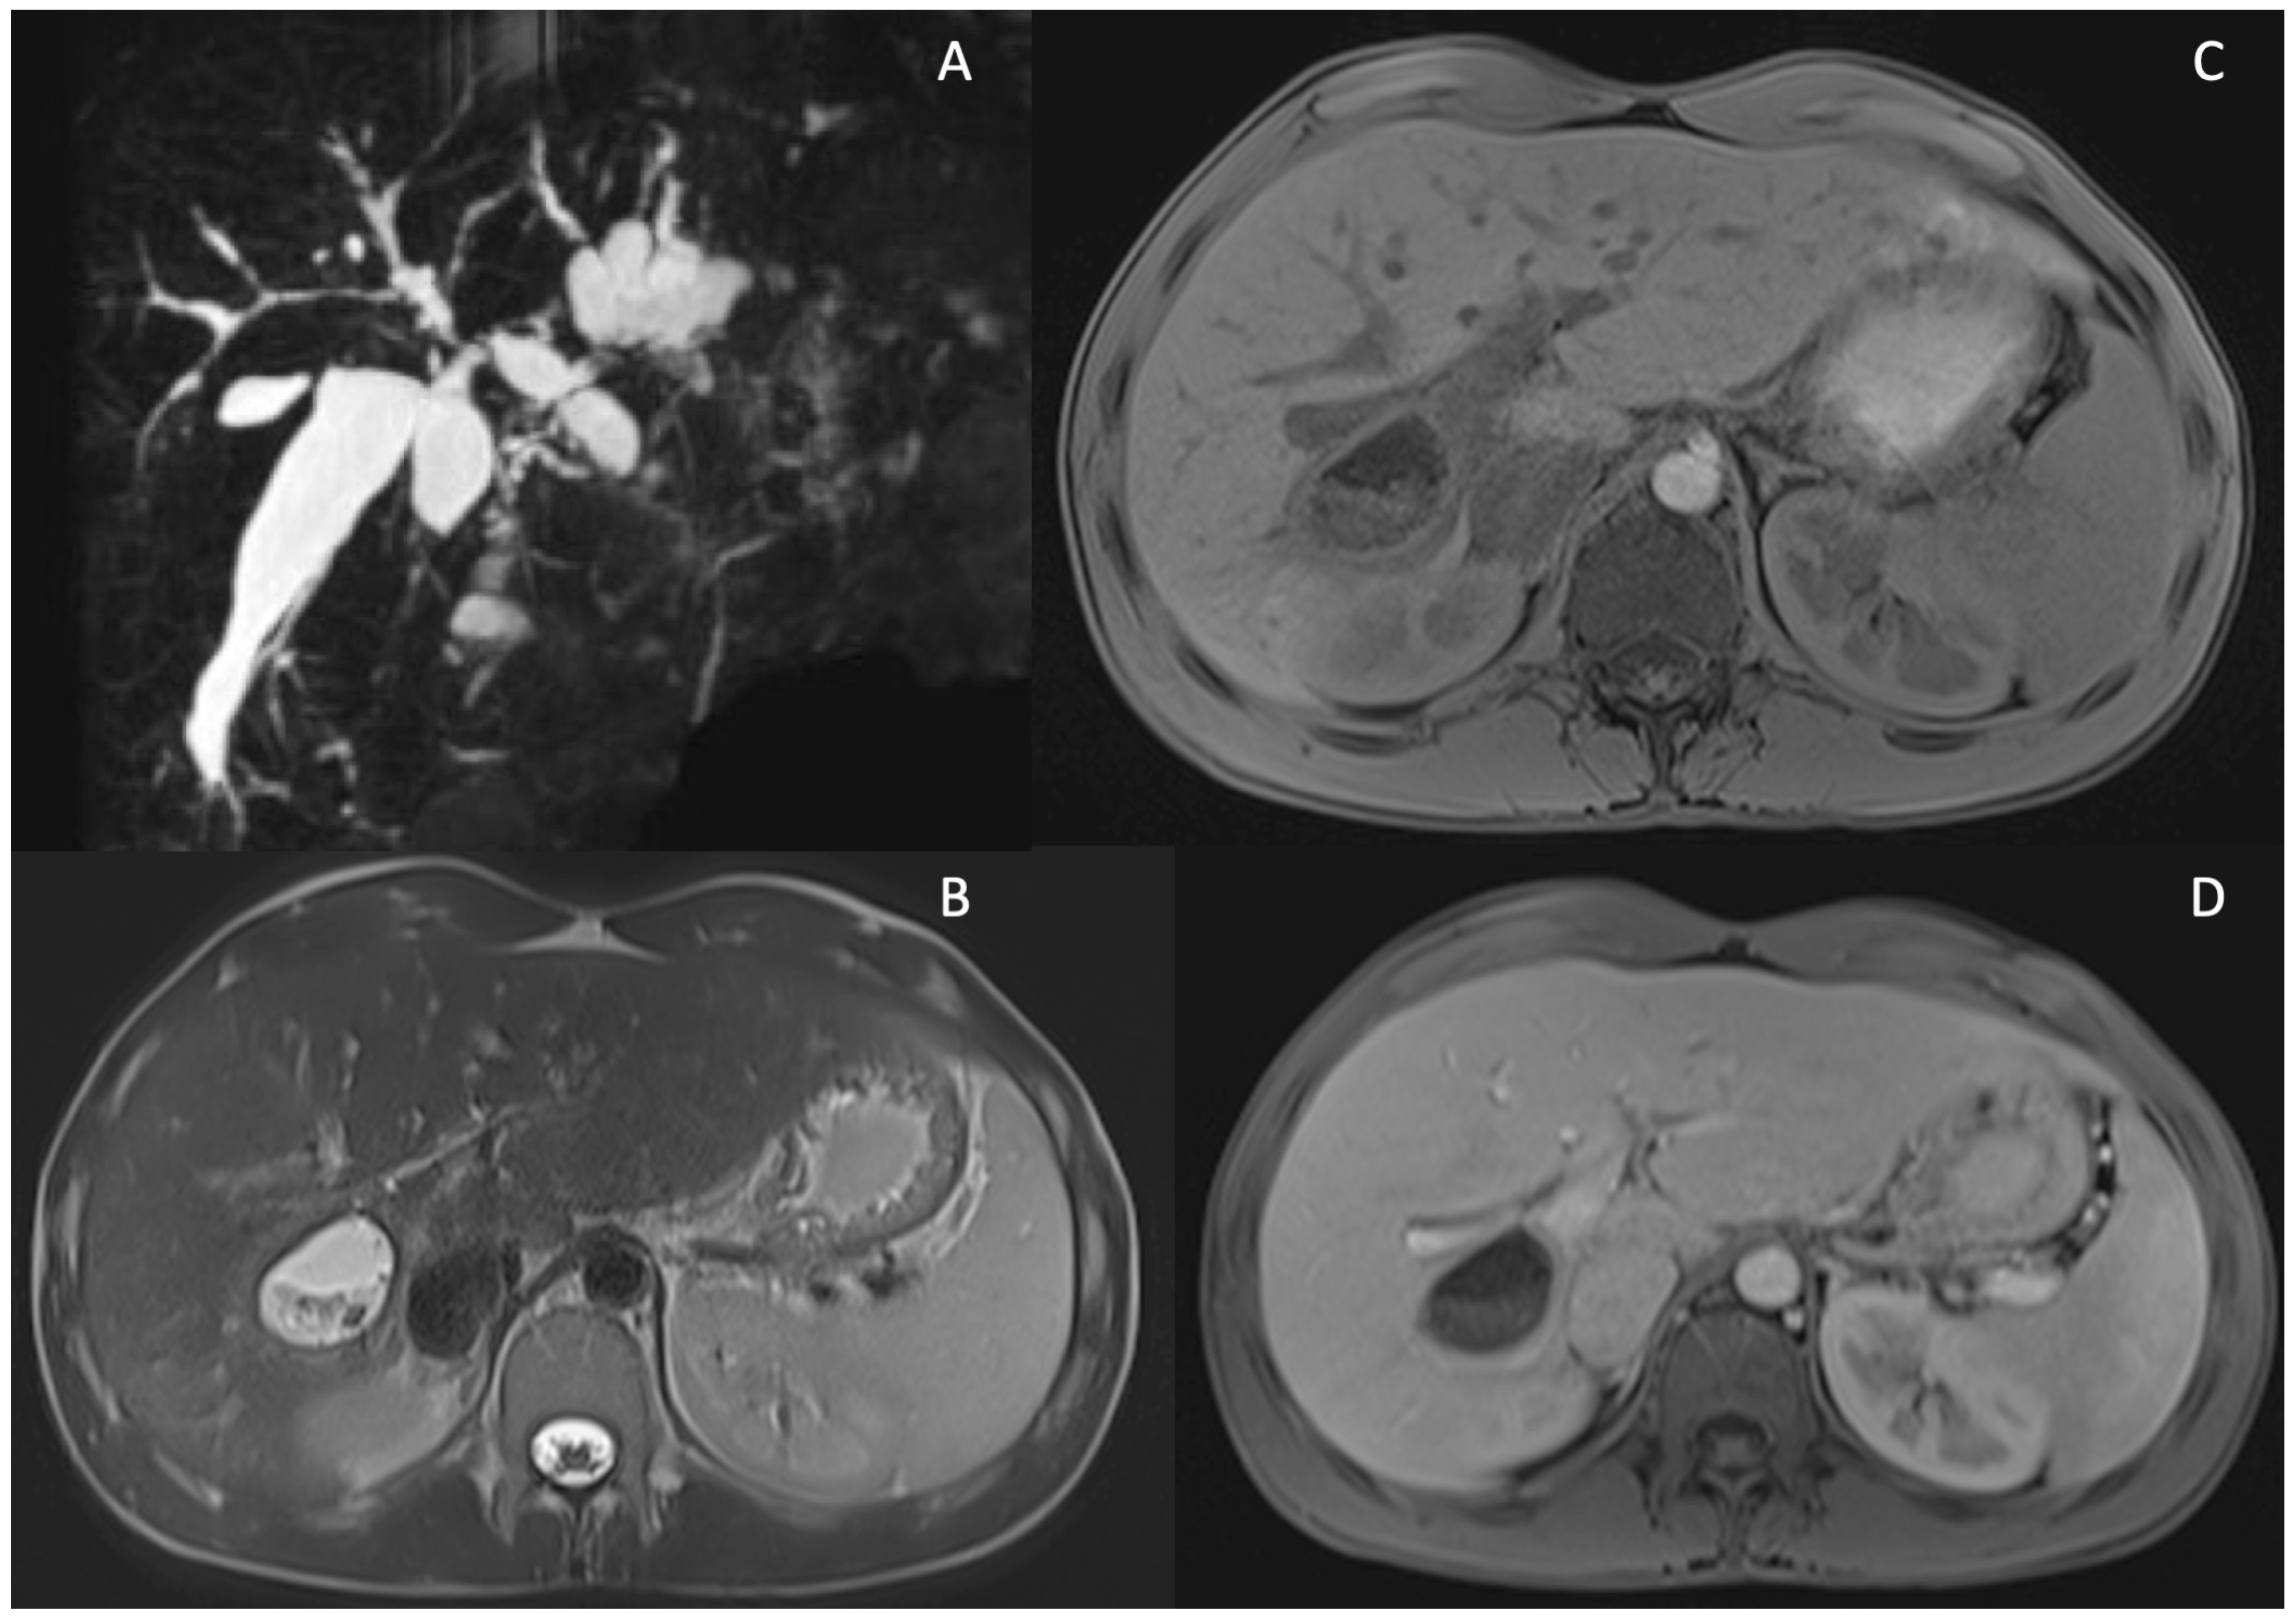

5. Technical Aspects of MRI in PSC

6. Cholangiographic and Liver Parenchymal Changes in PSC